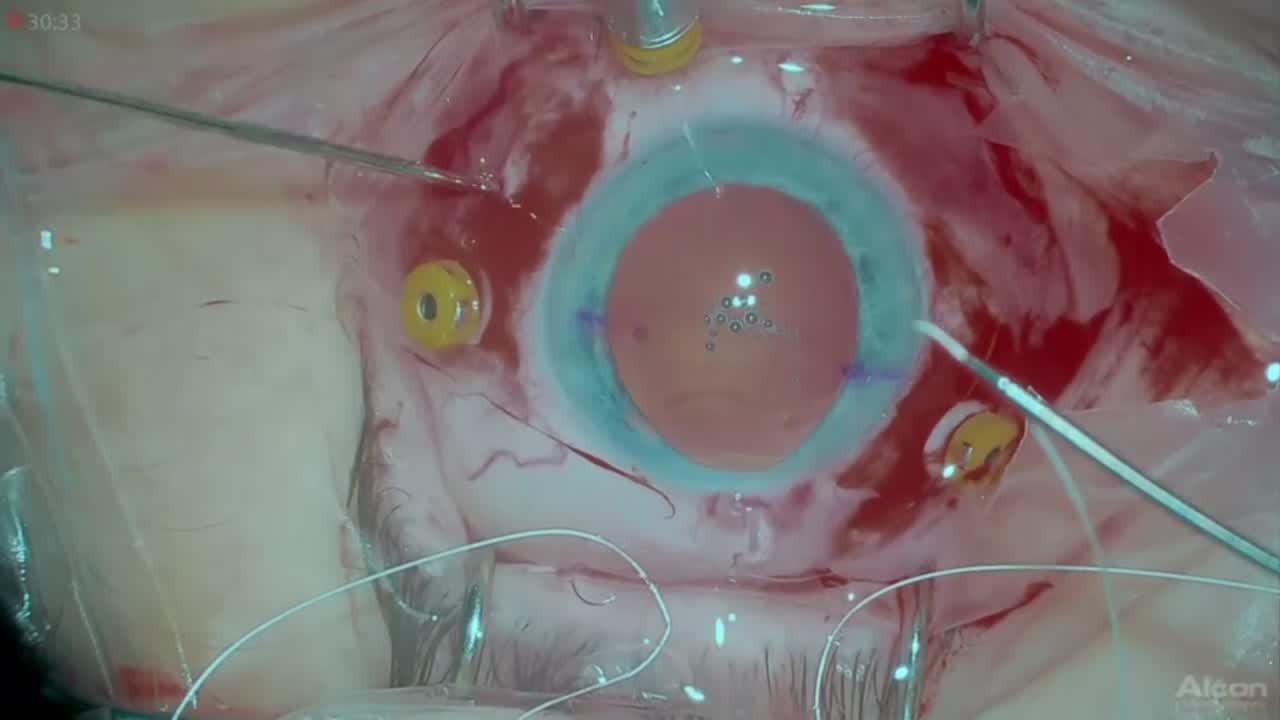

Stretched Macula

Stratos Gotzaridis, MD